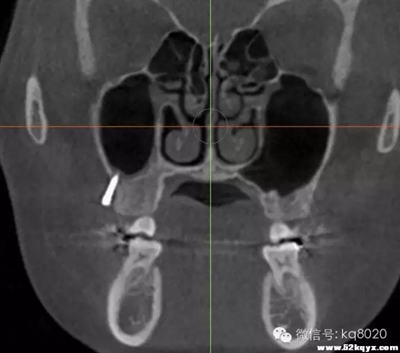

上下頜磨牙后區(qū)(56之間居多):

危險因素:此處無重要血管神經(jīng),相對安全,但牙根與上頜竇較近,避免傷及植入位置和角度:應(yīng)從膜齦聯(lián)合處或其牙合方植入,大約距離牙槽嵴頂5-6mm的位置,

原因

①此處牙根間隔最大;

②避免植入后粘膜覆蓋牙根之間;支抗釘位于牙根之間,與牙體長軸成30-45°角

大?。河捎诤笱绤^(qū)牙根間距相對較小,骨質(zhì)疏松,但承受力值較大,宜選用8×1.4mm,且無切削頭設(shè)計(jì)支抗釘